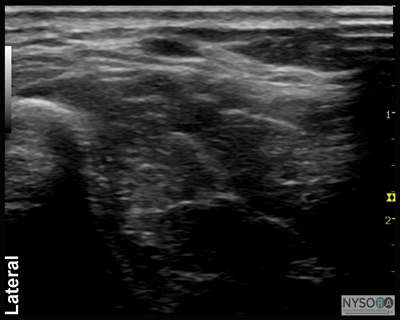

Ulnar Nerve The ulnar nerve is located medial (ulnar side) to the ulnar artery from the level of the midforearm to the wrist. This provides a useful landmark. A linear transducer placed at the level of the wrist crease will show the hyperechoic anterior surface of the ulna with shadowing behind; just lateral to the bone and very superficial will be the triangular or oval hyperechoic ulnar nerve, with the pulsating ulnar artery immediately next to it (Figures 4A and B and 5A and B). Unlike the median nerve, there are fewer structures (tendons) in the immediate vicinity that can confuse identification; however, the same confirmation scanning technique can be applied. Sliding the transducer up and down the arm helps verify that the structure is the ulnar nerve by following the course of the ulnar artery and looking for the nerve on its ulnar side.

Figure 5: (A) Sonoanatomy of the ulnar nerve (UN) at the wrist. US, ulnar artery. (B) Needle path to reach the UN at the wrist and approximate spread of the local anesthetic (area shaded in blue) to anesthetize the UN.